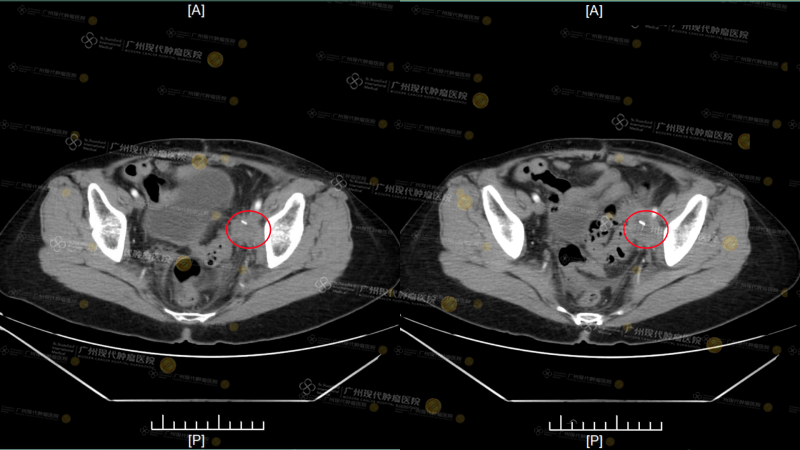

Sau khi từ chối điều trị, dường như Phù Ái Cầm đã từ bỏ mọi hy vọng, chỉ muốn tận hưởng quãng đời còn lại. Tháng 8 năm 2025, khối u và cơn đau lại ập đến dữ dội. Hạch lympho vùng chậu tái phát, to lên khoảng (3.9*3.3cm), chèn ép dây thần kinh ở chân, khiến chân trái sưng nghiêm trọng; gan cũng xuất hiện ổ di căn mới, khoảng (0.9*1.6cm). “Khi đó tôi chỉ có thể dựa vào thuốc giảm đau liều cao để duy trì giấc ngủ mỗi ngày.” Đau đớn và bất lực bám theo bà suốt ngày đêm, khiến bà không khỏi truy hỏi trong những lời cầu nguyện: “Lẽ nào quãng đời còn lại của tôi chỉ có thể như thế này thôi sao?”

(Kết quả CT này là kết quả kiểm tra nhập viện tại bệnh viện chúng tôi vào ngày 22 tháng 9)